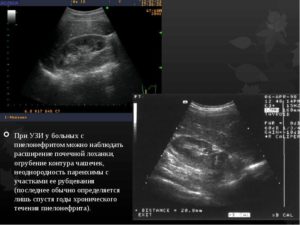

- пиелонефрит;